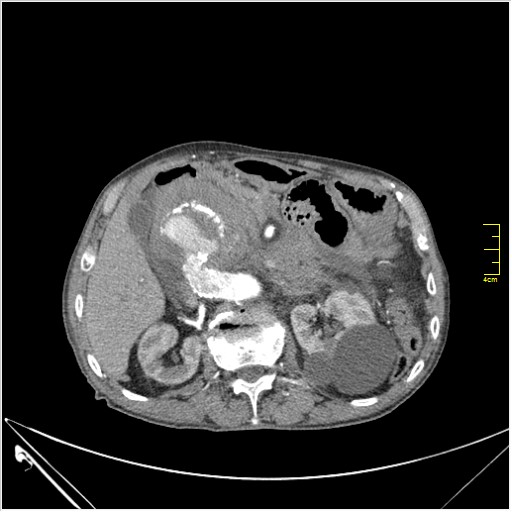

КТ брюшной полости. Мужчина с пальпируемой опухолью в животе

Пациент Т. 64 года, обратился на КТ брюшной полости амбулаторно (!), по направлению семейного врача с диагнозом abdominal mass, буквально: образование брюшной полости.

ИМХО простые кисты.Uzgraph писал(а):Случай интересный - ногу сломишь. Вроде бы анефризма брюшной аорты(особенно по УЗИ), но что тогда за образования сидят на левой почке - онкология?

Huge abdominal aorta aneurism. Simple renal cortical cysts (Bosniak type 1).